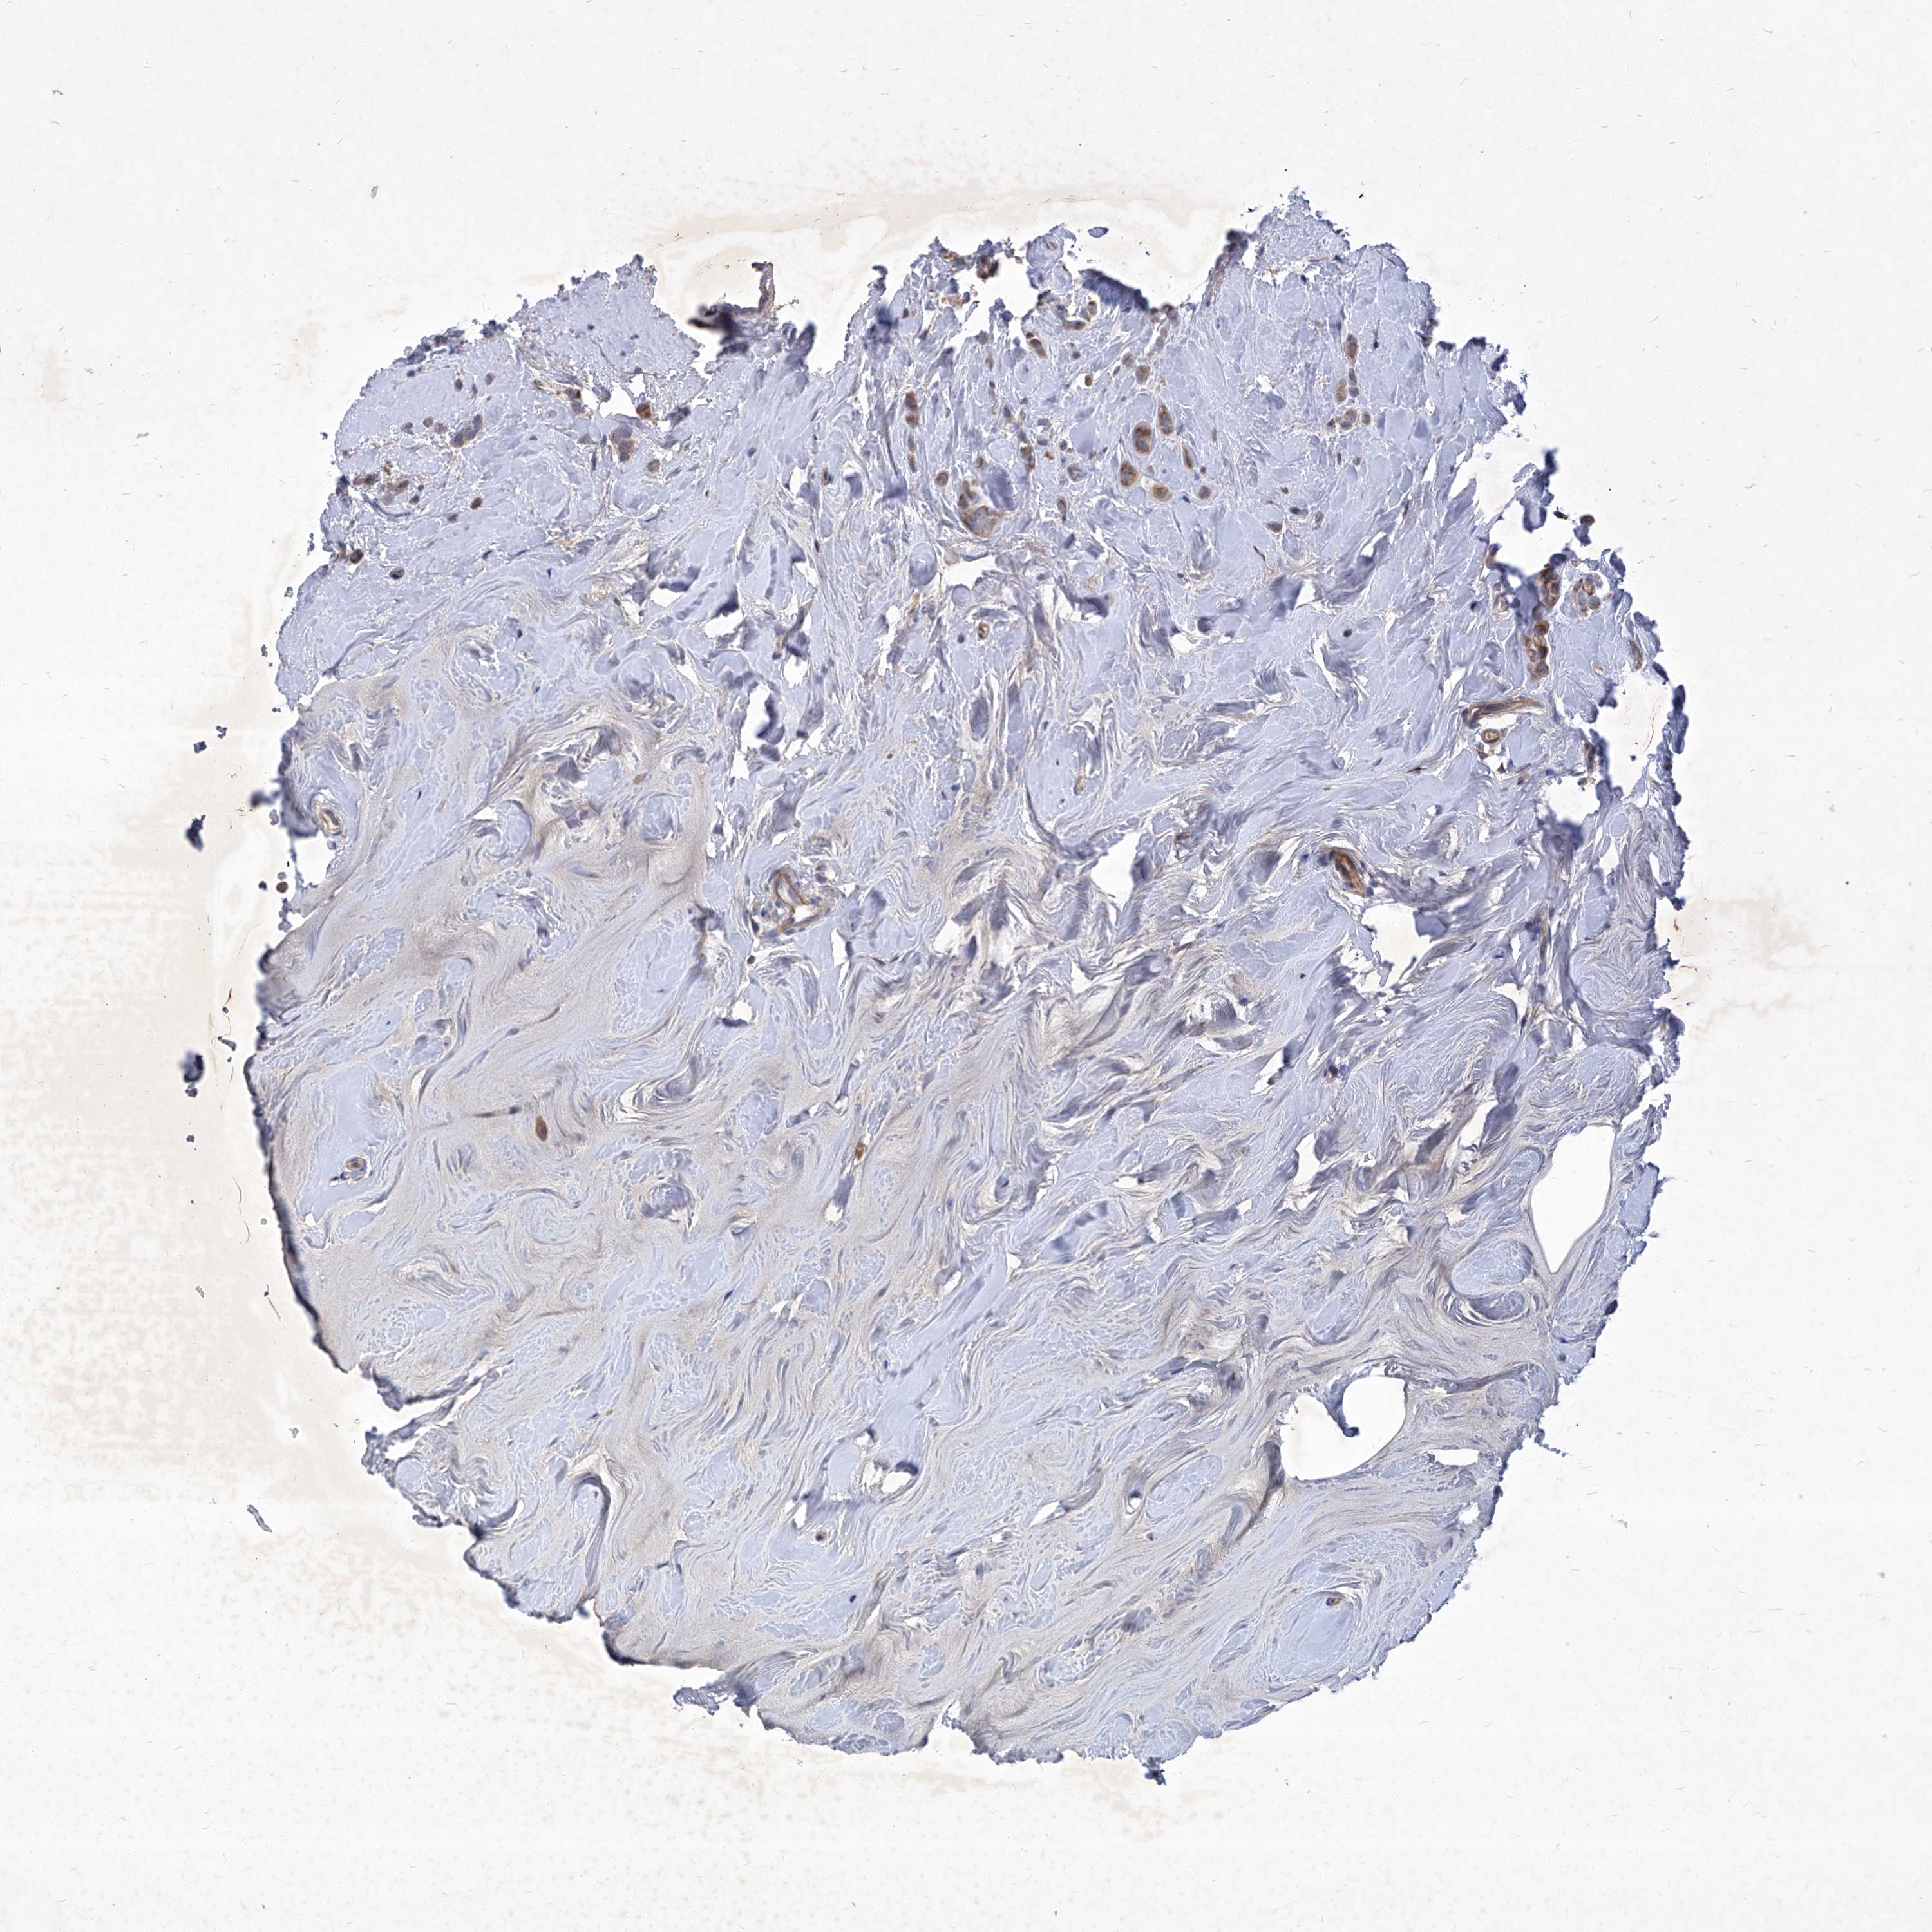

CANCER BREAST CANCER Show tissue menu

BRCA TCGA BRCA VALIDATION PROTEIN EXPRESSION

Breast cancer

Human cancer